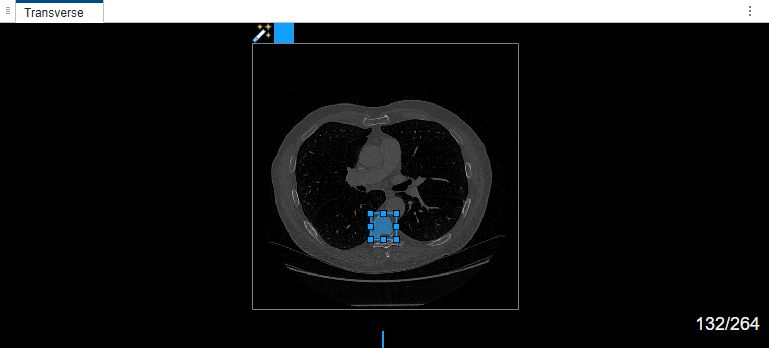

Select label Type1. Draw a bounding box around the object to segment in the transverse plane of the volume.

If you are segmenting objects in a medical image or a 2-D slice image of a medical volume for the first time in the app, and if you are not using a GPU, the MedSAM algorithm takes some time to extract embeddings for the image. In this case, the app displays the Running MedSAM model dialog box.

Once the MedSAM algorithm extracts the embeddings of the image, you can adjust the bounding box.